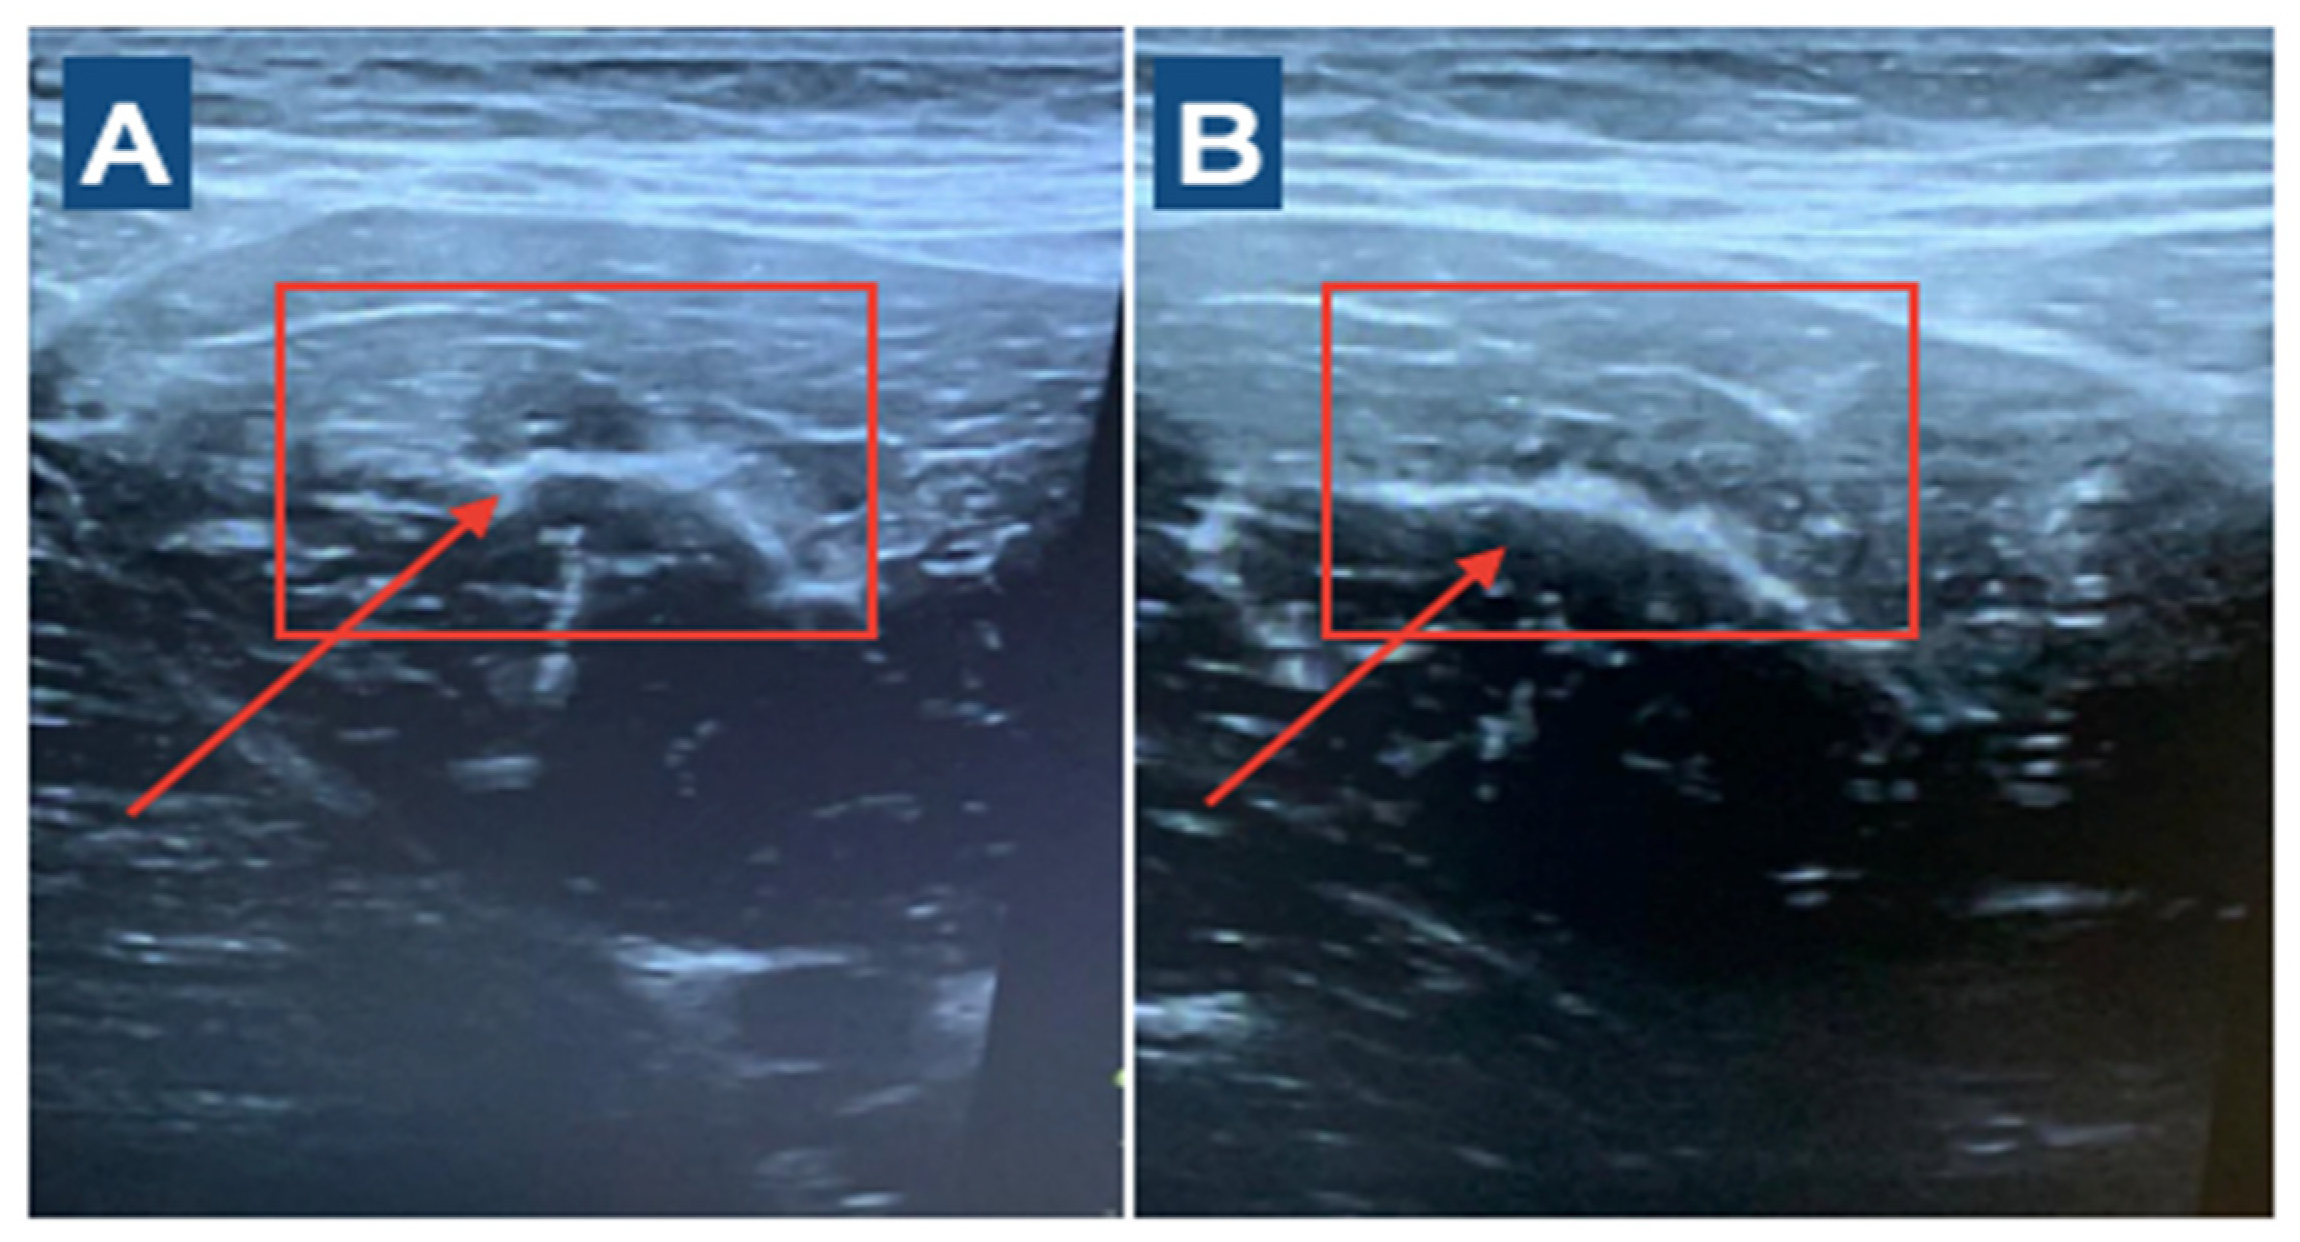

The player was clinically diagnosed by ultrasound [15] and subsequently underwent invasive physiotherapy treatment with percutaneous musculoskeletal electrolysis (PNE) with a dry needling needle. The decision to use this technique is supported by the club’s medical staff, the results obtained from previous injuries and the wide experience in the use of this technique. In addition, we have previously shown its efficacy in muscle injuries [11]. Electrolysis was performed 48 h after injury under ultrasound control and ultrasound-guided treatment at an intensity of 2 mA for 3 s and repeated five times [11] (Figure 1). A physiotherapist with more than 5 years of experience in ultrasound evaluation and over 7 years of experience in invasive therapy applied the PNE technique. The rehabilitation and reconditioning program started at 24 h post-PNE. It was based on a previously validated program that we have developed for adductor longus injury [10,11]. In addition, the tissue repair process was assessed using an ultrasound scan every 4–5 days to evaluate the evolution of the process and to be able to manage the subsequent loads that were applied to the injured tissue.

Figure 1. (A). Initial 48 h post-injury. Ultrasound imaging shows muscle fiber discontinuity at the level of tear. (B) Ultrasound imaging at 9 days post-PNE.